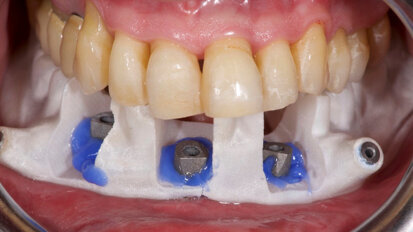

How to give a second life to third molars: A case series with follow-up

Dental autotransplantation entails extracting and repositioning a tooth into a different site in the mouth of the same patient. A successfully transplanted ...